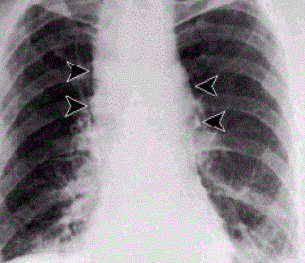

Bijoy E. John, MD; Amado Freire, MD

<p>A 58-year-old man with a history of a seizure disorder was hospitalized with acute-onset shortness of breath immediately following a tonic-clonic seizure. He was afebrile; in respiratory distress;...